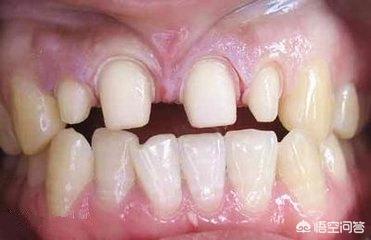

首先,生理性牙缝过大。多见于门牙,门牙牙缝过大部分是因为唇系带附离太低造成的,可以通过牙齿矫正,是牙齿慢慢移动到正常整齐的位置,来缩小牙缝。

其次,牙齿排列畸形成缝。如果是因为牙齿排列畸形形成的缝隙,建议可以做烤瓷牙冠或者选用正畸治疗。

牙列不齐或天生牙齿稀疏

就是牙齿长得不整齐,或者天生牙齿比较小,牙缝比较大,容易卡主食物。